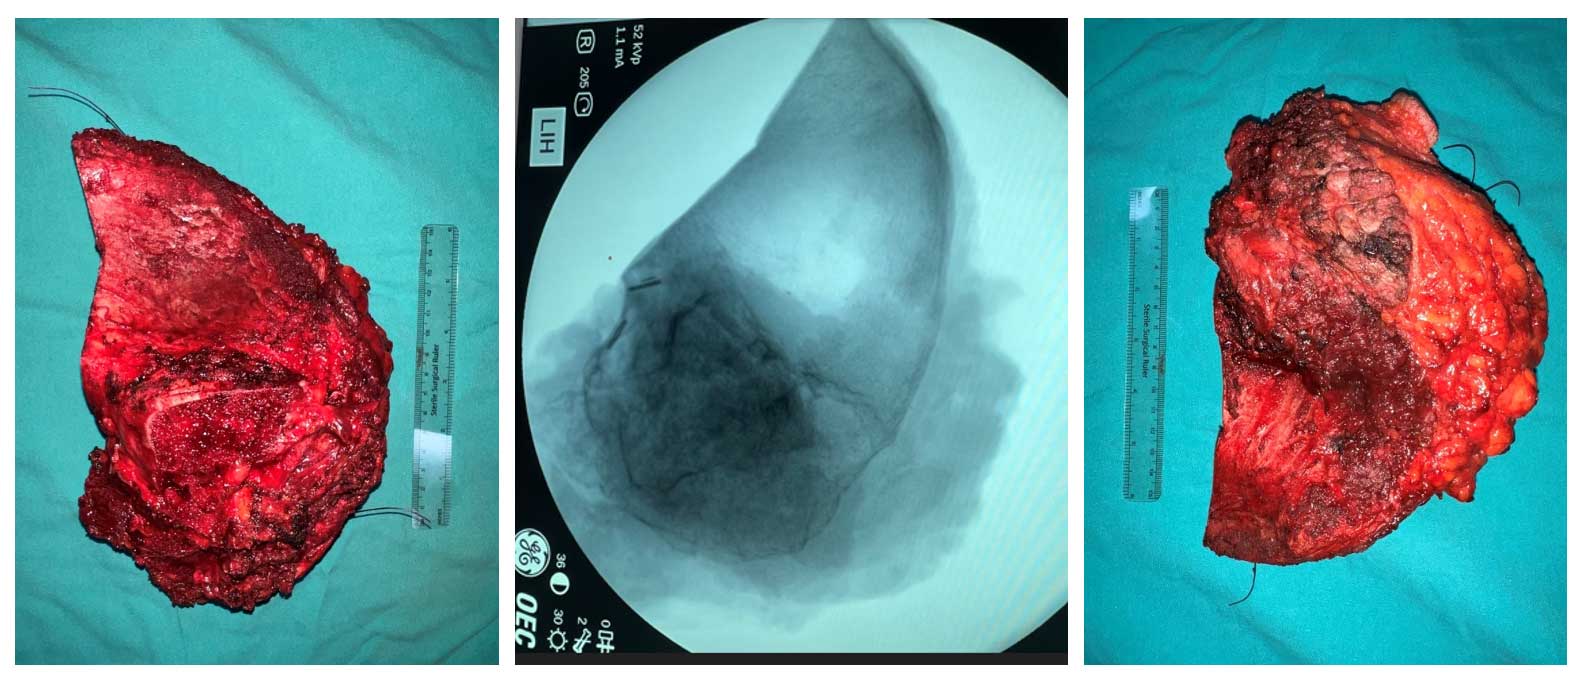

Ameliyat Esnası: Çıkarılan tümör dokusunun klinik ve radyolojik görüntüsü.